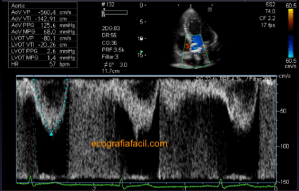

139. Ecocardiografía. Estudio Paraesternal Eje Largo.

141. Mediciones de los planos paraesternales.